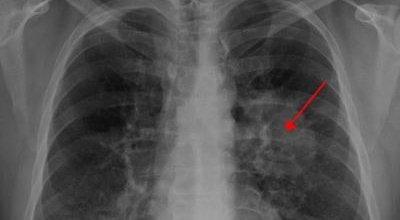

폐암 검사는 X-ray를 통해서 검사하는데 , 크기가 작거나 구석에 위치한 경우 확인이 어려운 경우도 있습니다. 그리고 조직 검사를 통해서 정확한 진단을 하게 돼요. 폐암이 발견되면 종양의 크기나 전이 여부 , 위치에 따라서 수술 여부를 결정하게 돼요.